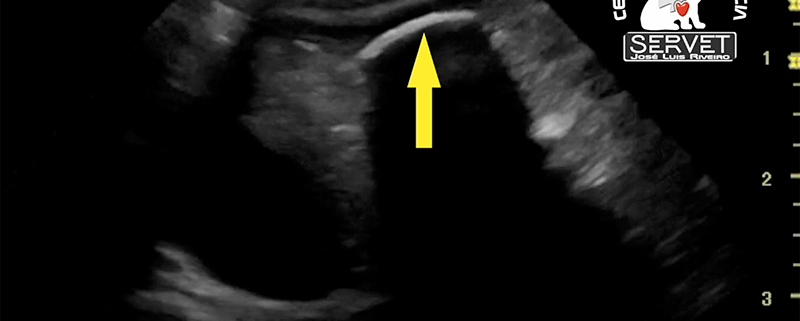

Ecografía cuerpo extraño gástrico Servet urgencias veterinarias

/0 Comentarios/en Diagnóstico por imagen, Ecografia, Noticias, Urgencias/por José Luis Riveirola ecografía abdominal tiene la capacidad de identificar un cuerpo extraño, aunque este sea radiotransparente